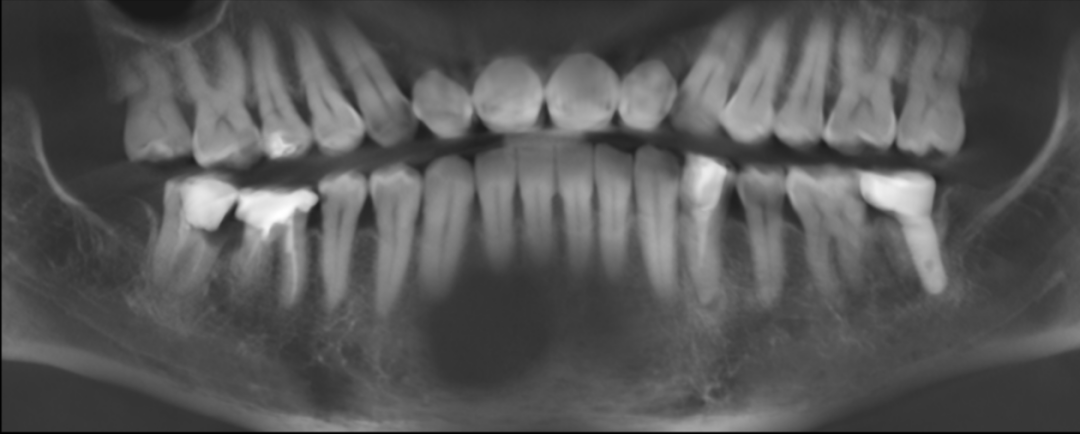

●46、47牙见大面积银汞填充物,边缘密合度差,无松动,叩痛(—),牙髓温度测试无反应

●46、47牙冠部见大面积银汞充填影像,充填物边缘影像见低密度影像,根管内见根充物影像(欠充),根尖未见低密度影像,牙槽骨宽度及高度条件良好